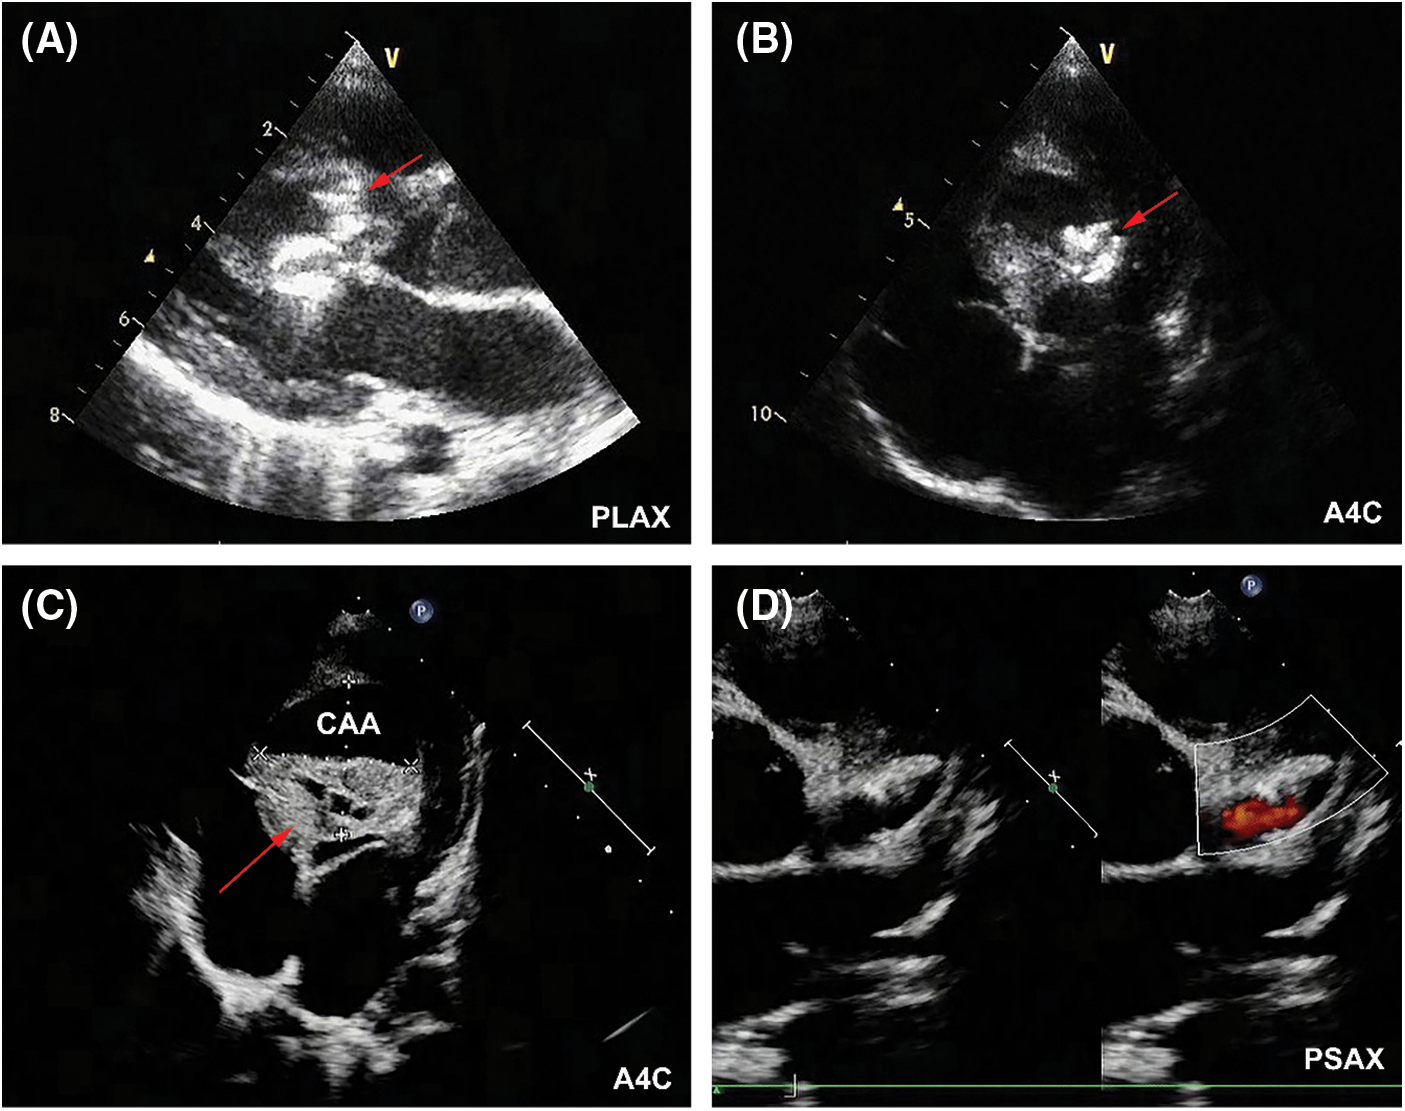

At postoperative day 1, the patient experienced elevation of cardiac troponin T (TnT, peak of 448 pg/mL; normal values < 14 pg/mL) and creatine kinase-MB (CK-MB, peak of 41.9 U/L; normal values < 24 U/L). Although no elevation of ST segment or ST-T changes was detected in ECG, her 24-h holter monitoring showed period of junctional escape rhythm and aberrant ventricular conduction, indicating potential myocardial ischemia (Figs. 4A and 4B). TTE demonstrated both devices were well located, without apparent residual shunt (Figs. 5A and 5B). Thrombus formation was detected within the CAA (Fig. 5C), and LCA ostium was still dilated (Fig. 5D). The patient was given dual antiplatelet therapy with aspirin (5 mg/kg) and clopidogrel (1 mg/kg). The remaining postoperative course was uneventful. Her ECG returned to normal sinus rhythm at postoperative day 2, and level of CK-MB returned to normal level (21 U/L). The patient recovered well and was discharged at postoperative day 7 post procedure without complications.

Figure 5: TTE results at postoperative day 1. (A) The AVP II (red arrow) was located at the inlet of fistula without residual shunt in parasternal long-axis view (PLAX). (B)The ADO II (red arrow) was located at the outlet of fistula without residual shunt (A4C). (C) Thrombus formation (red arrow) was detected within the CAA (A4C). (D) LCA was still significantly dilated (PSAX)

The patient was prescribed with dual antiplatelet therapy for a total of 6 months. Follow-up TTE at 2 years showed shrinkage size of CAA, and the two devices were in proper position without residual shunt (Figs. 6A and 6B). The diameter of LCA ostium has significantly reduced (Fig. 6C). LV function was normal (LV ejection fraction 62%), without signs of regional wall motion abnormality. Follow-up ECG at 2 years showed normal sinus rhythm (Fig. 6D). The patient was in good clinical conditions, without cardiovascular symptoms or signs of late complications such as myocardial infarction or thromboembolism.

Figure 6: 2-year follow-up results. (A) Shrinkage size of CAA was demonstrated in TTE (A4C). Red arrow indicated the CAA. (B) Red arrow indicated the implanted device (PLAX). (C) Size reduction of LCA ostium was detected (PSAX). (D) ECG showed normal sinus rhythm